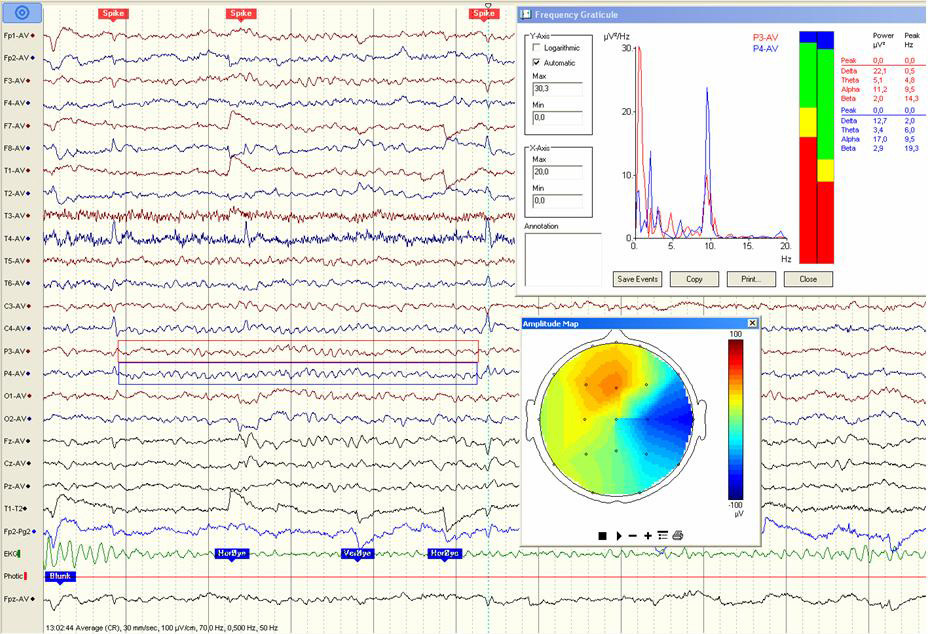

En visuell skjønnsmessig vurdering av EEG-bakgrunnsaktivitetens frekvens og amplitude blir også foretatt. Denne vurderingen kan unntaksvis suppleres med en spektralanalyse av frekvensinnholdet i EEG (QEEG) og topografisk kartlegging (18). Spektralanalysen er tilgjengelig i noen typer EEG-programvare, og et eksempel er vist i figur 1. Den kliniske betydningen av metoden er fortsatt omdiskutert (19), og den brukes ikke rutinemessig ved klinisk nevrofysiologiske avdelinger i Norge.

På den annen side er det noen nevropsykiatriske miljøer som anbefaler spektralanalyse som et supplement til klinisk AD/HD-diagnostikk (20) på grunn av en statistisk økt mengde langsomme thetabølger hos disse pasientene (6, 7, 21, 22). Det er mulig at disse funnene har en sykdomsassosiert nevrobiologisk betydning, men en alternativ tolkning er at AD/HD er assosiert med økt døsighet på dagtid (23). I vanlig klinisk EEG-diagnostikk kan også medikamenter, søvndeprivasjon og andre feilkilder forårsake økt langsom thetaaktivitet eller nedsatt alfafrekvens (24). Disse funnene bør det forskes mer på, men inntil videre kan vi ikke bruke spektralanalyse av frekvensinnholdet i EEG som et tilstrekkelig pålitelig supplement i klinisk AD/HD-diagnostikk.

Etter vår erfaring er en ukomplisert AD/HD-diagnose av og til forbundet med fokale sentrotemporale spikes (fig 1). Klinisk betydning av slike funn er det ingen enighet om, men noen barn vil senere utvikle anfall og få diagnosen rolandisk epilepsi (benign barneepilepsi med sentrotemporale spikes) (25, 26). Det er også en usikker sammenheng mellom spiketetthet og symptomgrad (30, 35, 36). De fleste studier mangler kontrollgruppe, og det er usikkert om forfatterne feilaktig kan ha inkludert benigne epileptiforme varianter. Spikes finnes også hos friske barn. I våken tilstand er det rapportert forekomst av spikes hos 3 – 5 % (37) – (39) og under søvn hos 1,5 – 8,7 % (35, 37) (tab 1), men tilfeldig påvist epileptiform aktivitet hos ellers friske barn er oftest forbigående (38).